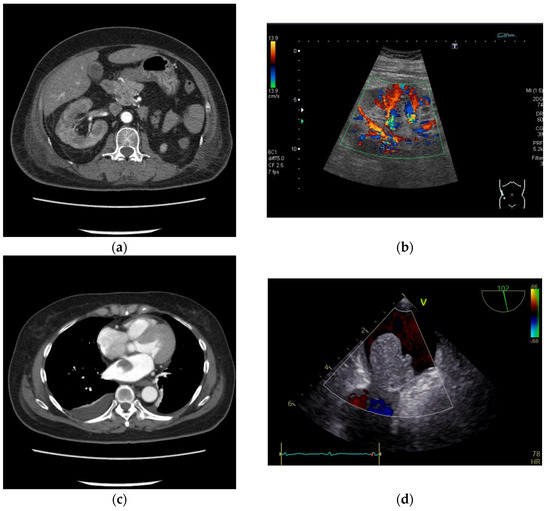

2. Case Presentation